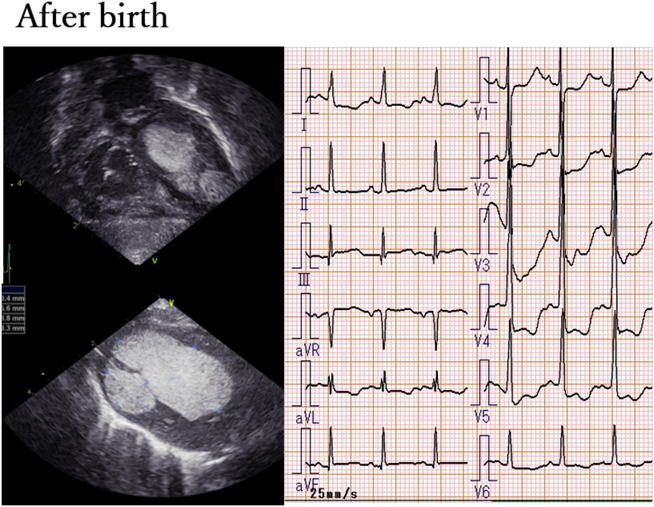

Fig. 1 Echocardiography and electrocardiography after birth

Transthoracic echocardiography demonstrates multifocal echogenic masses. There are 2 masses in most parts of the left ventricle (apex to outflow), resulting in mild outflow obstruction; 3 masses at the right ventricular apex and inflow and outflow tracts; and 1 mass at the right atrial appendage. On electrocardiography, a low ST level at V2 and a negative T wave at V3–V6 are detected. QTc=410 ms.